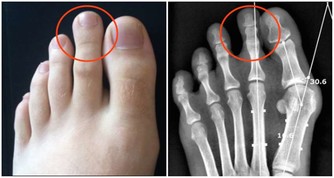

④四肢血管堵塞,或發生動脈硬化,可能很容易出現下肢動脈硬化閉塞症,下肢會發黑、疼痛,還會出現跛腳的症狀。